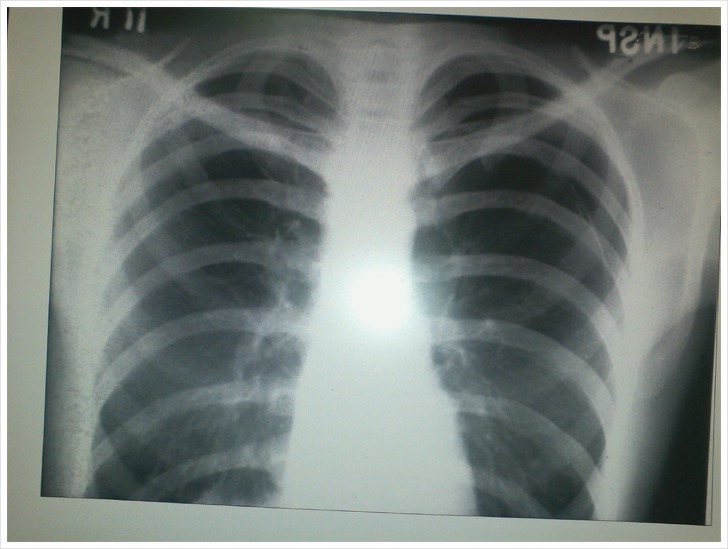

갈비뼈에 금이 갔을 때 느끼는 통증은 상당히 심각할 수 있습니다. 특히, 갈비뼈는 우리 몸의 중요한 장기인 폐와 심장, 그리고 내장을 보호하는 역할을 하기 때문에, 갈비뼈에 문제가 생기면 여러 가지 불편함을 겪을 수 있습니다. 기침이나 재채기 같은 일상적인 행동조차 고통스럽게 느껴질 수 있고, 심한 경우 숨을 쉴 때마다 통증을 느낄 수도 있습니다.

갈비뼈에 금이 갔을 때의 치료는 복잡합니다. 일반적인 골절과는 달리 갈비뼈에는 기브스를 씌울 수도 없고, 다리나 팔처럼 플레이트나 나사로 고정할 수도 없습니다. 이는 갈비뼈가 움직임이 많고 중요한 장기를 보호하는 역할을 하기 때문입니다.